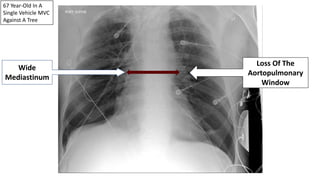

67 Year-Old In A

Single Vehicle MVC

Against A Tree

Wide

Mediastinum

Loss Of The

Aortopulmonary

Window

Traumatic

Pseudoaneurysm